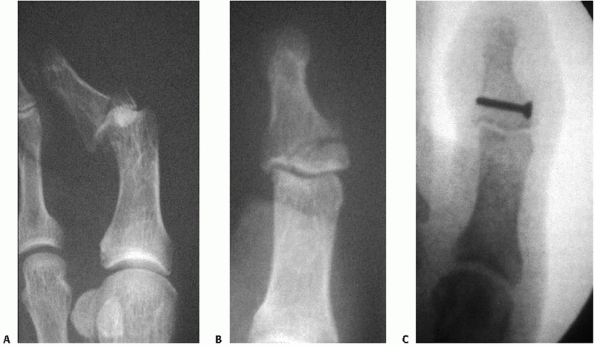

![]() |

FIGURE 60-17 Cuboid fracture involving the calcaneocuboid joint. A.

Preoperative lateral radiograph of injury at the calcaneocuboid joint. Note the fracture of the anterior process of the calcaneus contributing to the instability. B. Placement of the external fixator allows restoration of anatomic position. C. The articular surface is reduced and the void is filled with cancellous graft. D. The intact cortex is then reduced under the subchondral lip and held in place with screws secured to the medial wall of the cuboid. |